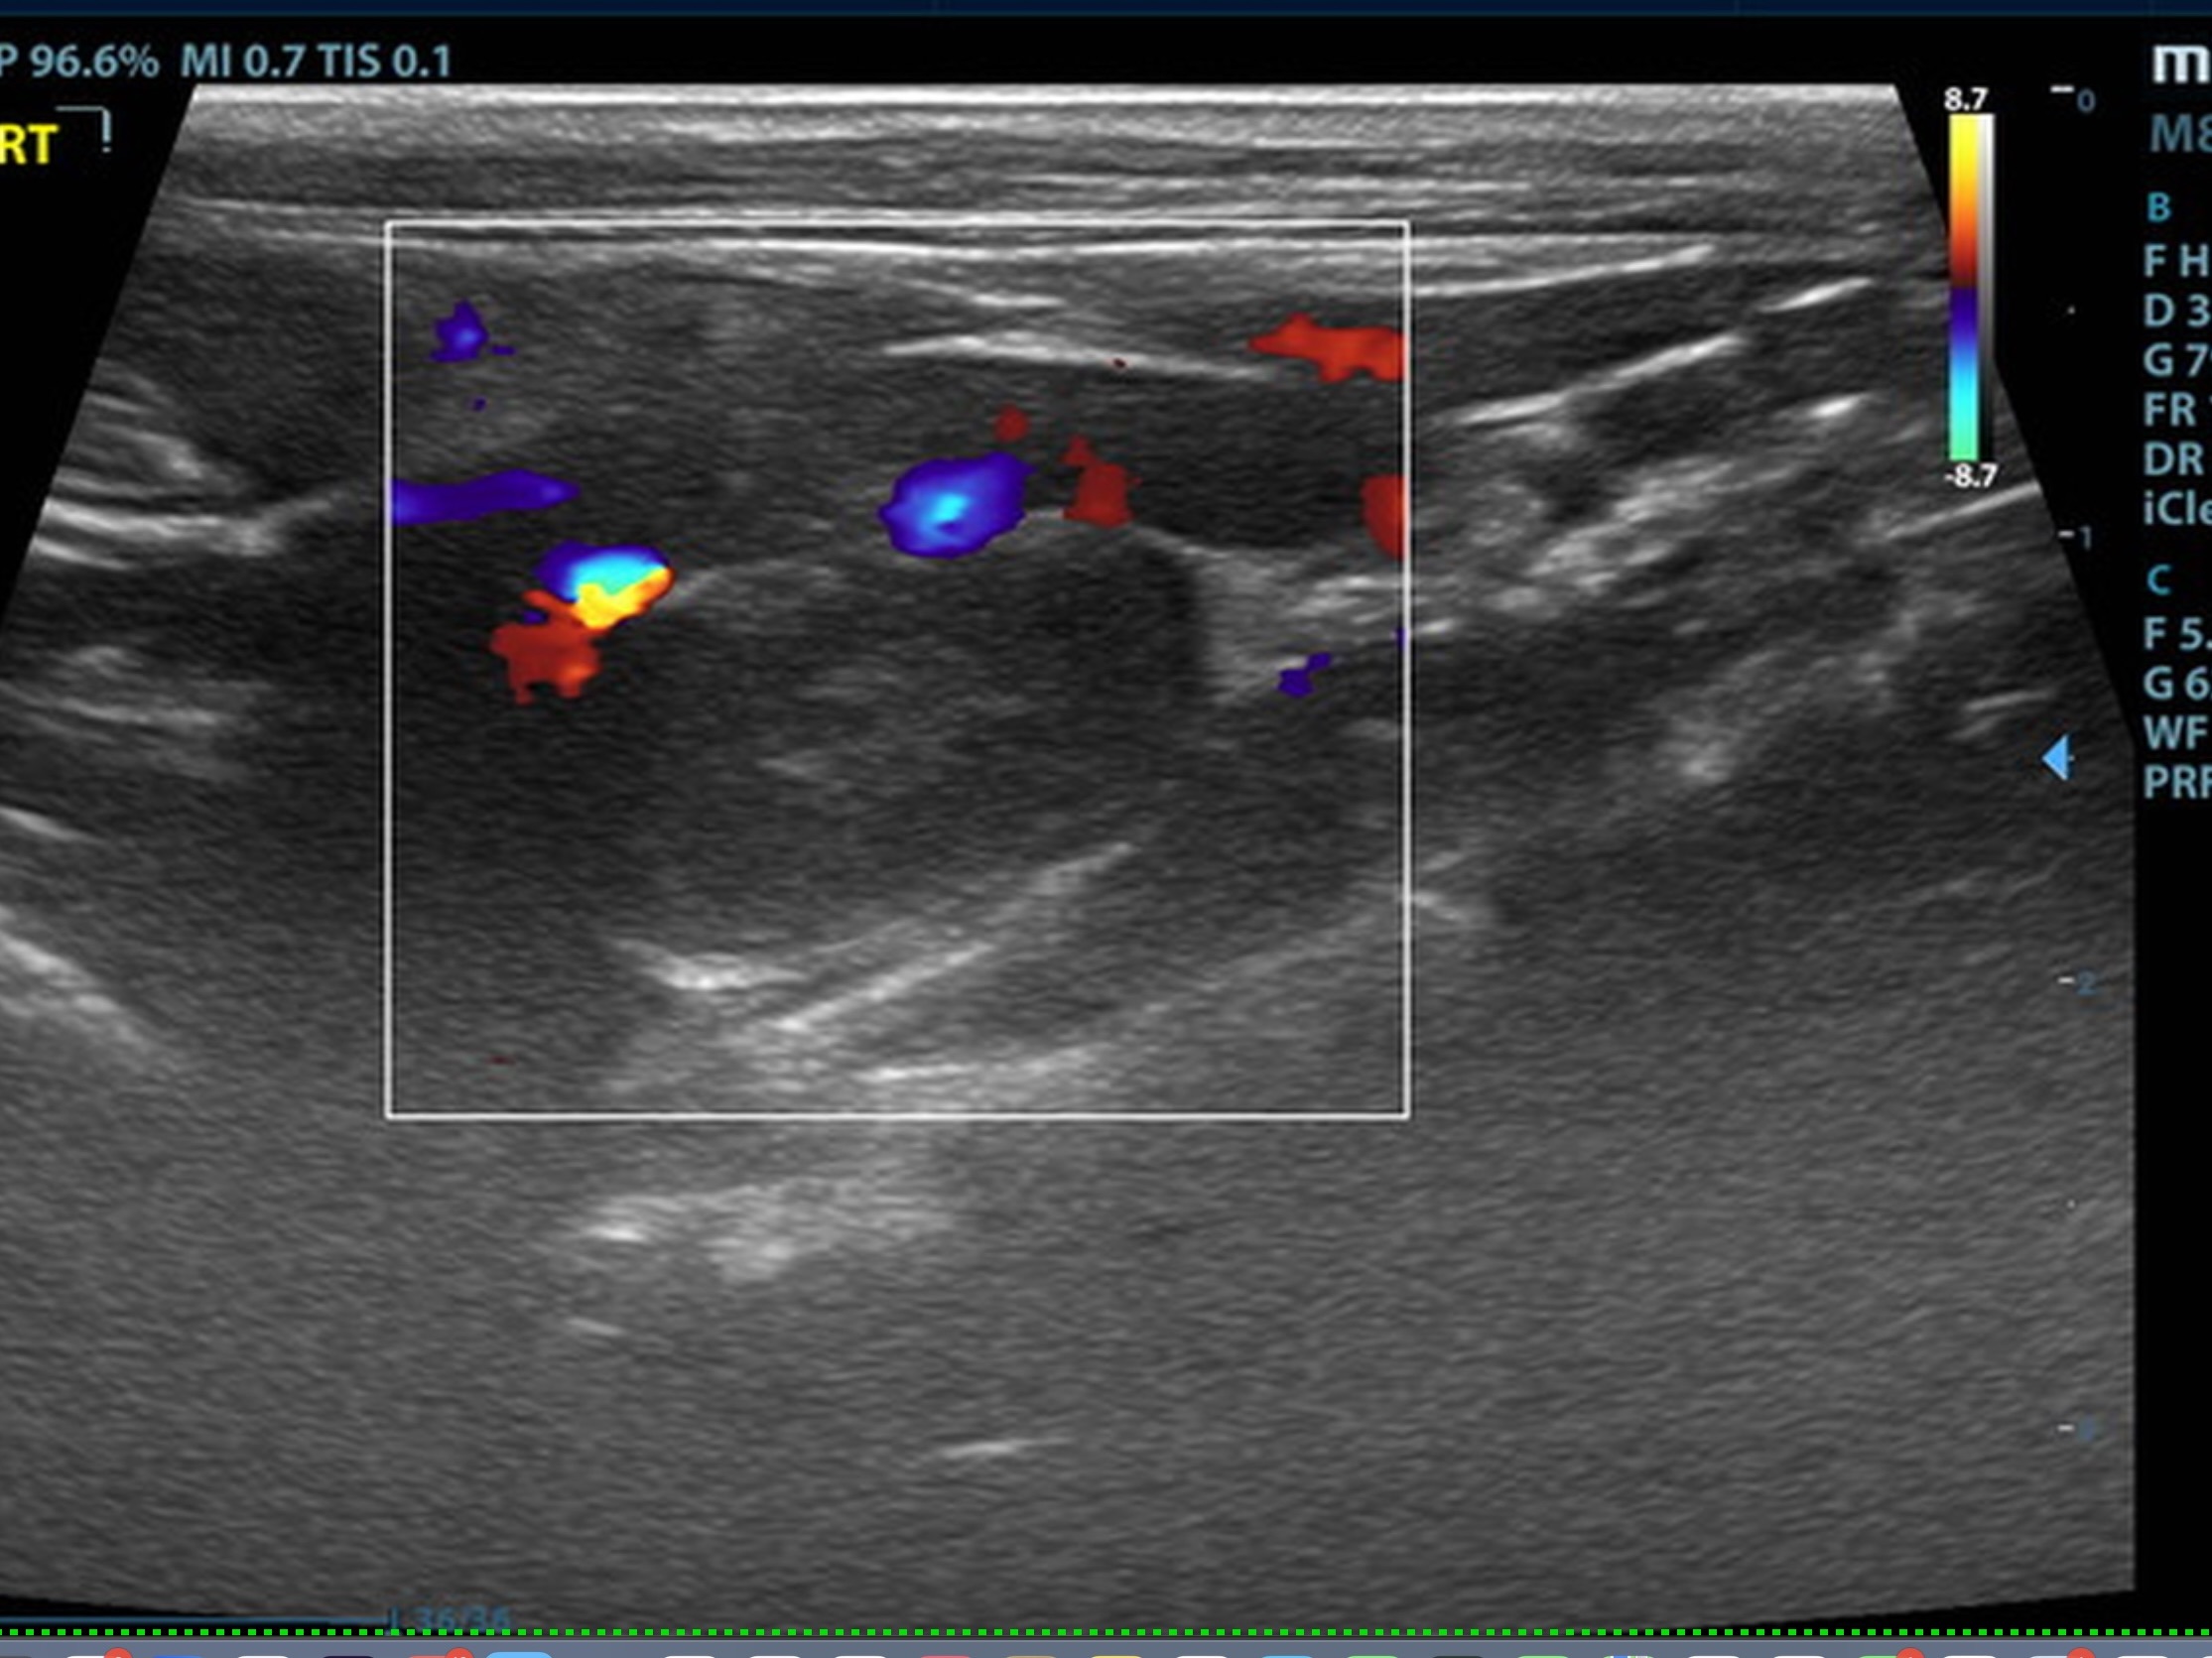

The right adrenal was enlarged and irregular, measuring 0.77 cm at the cranial pole and 0.30 cm at the caudal pole, with a caval invasion of 0.85 cm. Minor areas of mineralization noted. The left adrenal gland was recognized as normal. Mild variable GI thickening and echogenic submucosal changes. Some loss of renal curvilinear patterns regarding the capsule and cortico-medullary junction; increased echogenicity, mineralization.  Some hepatic parenchymal remodeling.

• Invasive right adrenal mass

Surgical consult warranted. The surgeon should be prepared for invasion of the vena cava at approximately 1.0 cm. Assessment of sodium to potassium ratio warranted. If hypokalemia present, aldosterone levels indicated. Serial blood pressures, chest radiographs warranted. No overt evidence of metastatic disease. The right adrenal pathology may not be overtly responsible for the weight loss. Malassimilation/maldigestion panel should be considered.